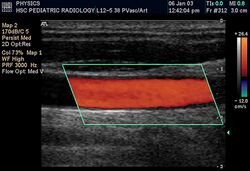

Duplex ultrasonography sometimes refers to Doppler ultrasonography or spectral Doppler ultrasonography.[3] Doppler ultrasonography consists of two components: brightness mode (B-mode) showing anatomy of the organs, and Doppler mode (showing blood flow) superimposed on the B-mode. Meanwhile, spectral Doppler ultrasonography consists of three components: B-mode, Doppler mode, and spectral waveform displayed at the lower half of the image. Therefore, "duplex ultrasonography" is a misnomer for spectral Doppler ultrasonography, and more exact name should be "triplex ultrasonography".[3]

Colour Doppler shows the direction of the blood flow in red or blue (either towards or away from the transducer). Meanwhile, spectral Doppler not only shows the direction of blood flow, it also shows the phases (pulsatility) and acceleration of the blood flow. Any sudden changes in direction of blood flow produces audible sounds on the ultrasound machine.[3]

There are no standards for displaying color Doppler. Some laboratories show arteries as red and veins as blue, as medical illustrators usually show them, even though some vessels may have portions flowing toward and portions flowing away from the transducer. This results in the illogical appearance of a vessel being partly a vein and partly an artery. Other laboratories use red to indicate flow toward the transducer and blue away from the transducer. Still other laboratories display the Doppler color map in accordance with published data, with red shift representing longer wavelengths (scattered) from blood flowing away from the transducer and blue representing the shorter wavelengths from blood flowing toward the transducer. Because of this confusion and lack of standards, the sonographer must understand the underlying physics of color Doppler and the physiology of normal and abnormal blood flow in the human body (see Red shift).[4][5][6]